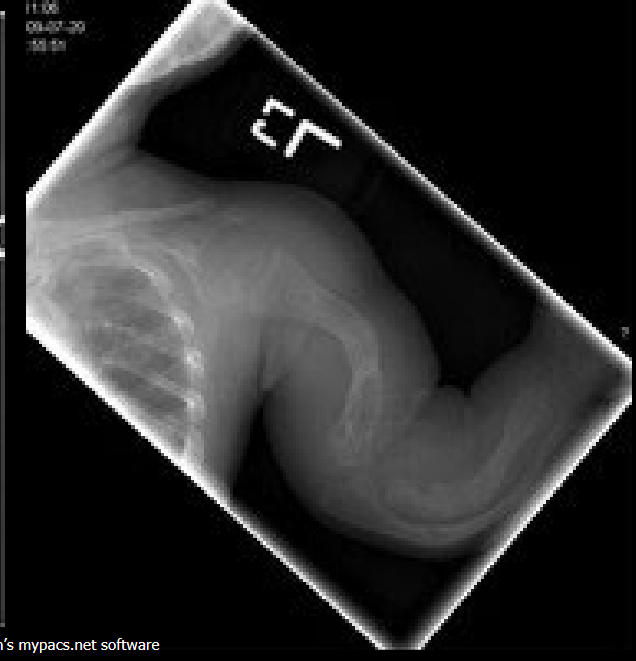

Define NAI.

Non-accidental injury/trauma; deliberate physical harm to a child.

Classic metaphyseal injury in NAI?

Corner/bucket-handle fracture.

Why are posterior rib fractures suspicious for NAI?

From squeezing the thorax.

Preferred initial imaging in suspected NAI?

Skeletal survey (not a ‘babygram’).